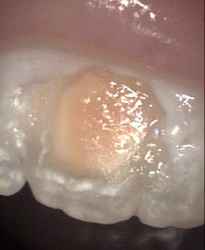

Top of back tooth

Restored